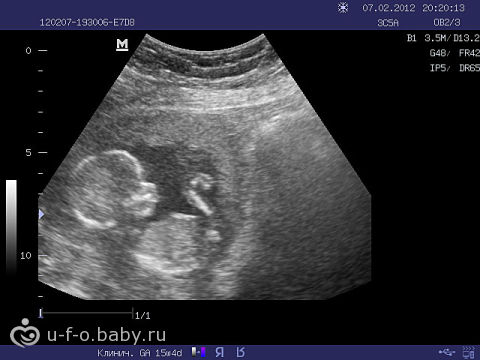

Photo échographie:

Selon vos caractéristiques individuelles (âge, maladie chronique) et votre bien-être, le médecin pourra vous proposer différents examens. Une échographie de routine n'est pas effectuée à la quinzième semaine. Mais si on vous le prescrit, il y a une toute petite chance de découvrir le sexe de l'enfant (si c'est un bon appareil et un médecin expérimenté). De plus, le spécialiste vérifiera l'état des membranes utérines, la quantité de liquide amniotique et l'emplacement du placenta. Sur l'écran du scanner, vous pouvez voir comment votre bébé bouge et à quel point il ressemble déjà à un petit homme.